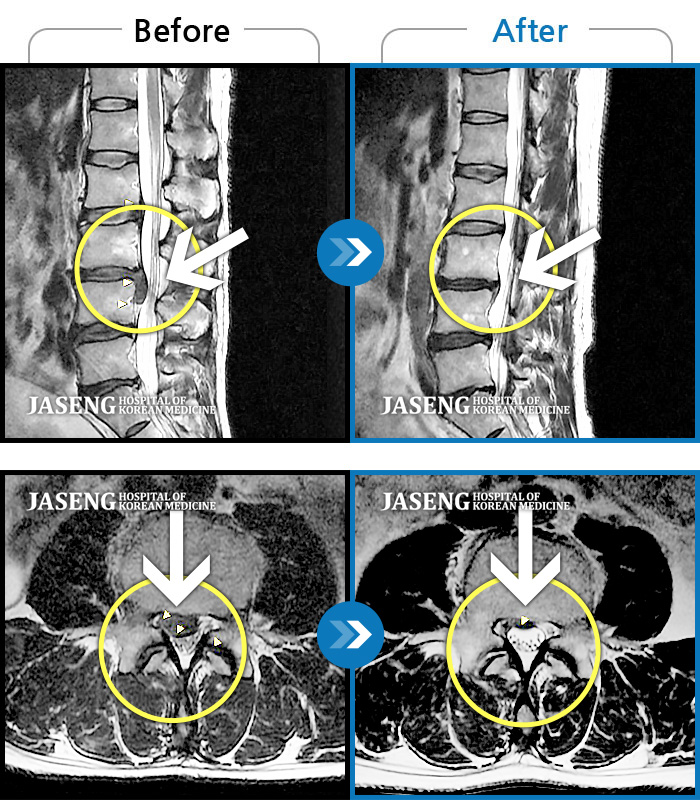

허리디스크

해운대 · 이상건 원장

허리통증 및 우측 하지 저림과 근력 저하

촬영시기

2018.02.05 ~ 2018.08.25